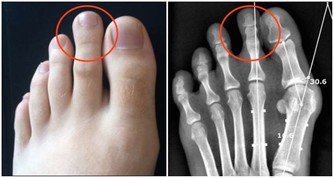

腸癌患者體內的腫瘤會阻塞腸道,妨礙糞便通過,進而導致便秘。

除了排便習慣的改變,結腸癌患者還有可能出現便血、腹痛、疲倦乏力、體重驟減等病症。